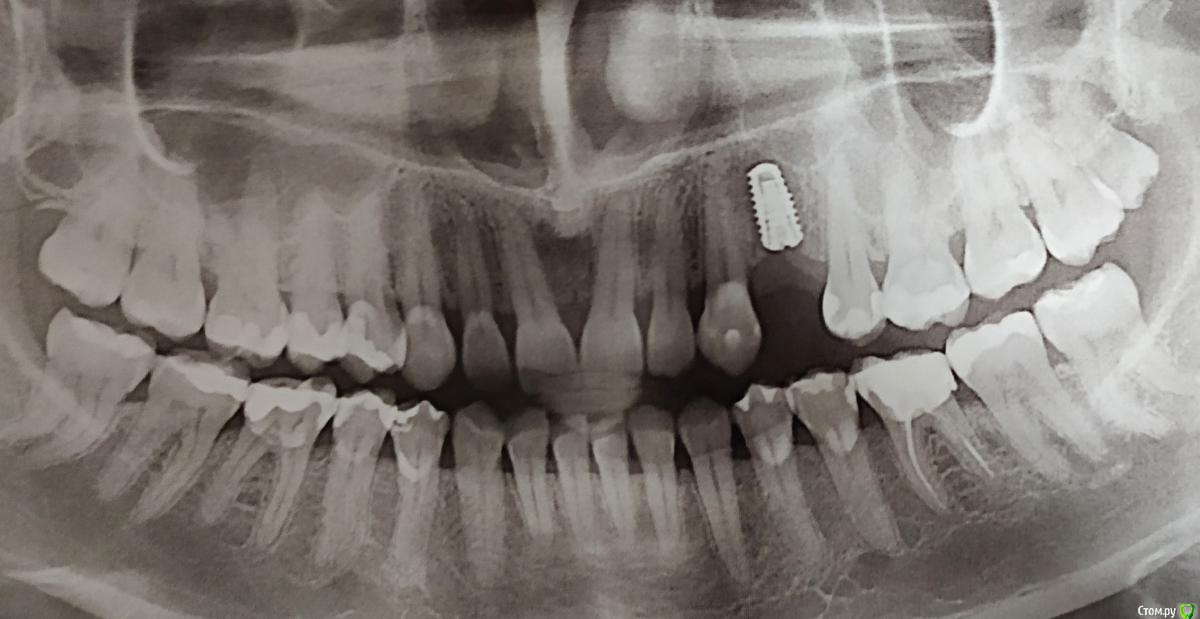

bogdana.ki Опубликовано 19 июня, 2019 Поделиться Опубликовано 19 июня, 2019 5 дней назад установили имплант. Врач говорит, что все хорошо, снимок сделать отказался. Сделала самостоятельно. Посмотрите, пожалуйста, все ли хорошо. Уже 4й день температура, насморк, горло красное. Спасибо Ссылка на комментарий

bogdana.ki Опубликовано 19 июня, 2019 Автор Поделиться Опубликовано 19 июня, 2019 Фото снимка Ссылка на комментарий

red_butler Опубликовано 19 июня, 2019 Поделиться Опубликовано 19 июня, 2019 по снимку все хорошо. Если есть сомнения покажитесь своему врачу и ЛОРу Ссылка на комментарий